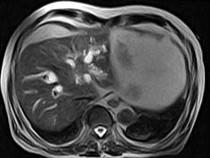

问题 男,43岁,右上腹痛,黄疸,AFP阴性,消瘦乏力,影像检查如下图,诊断为()

选项 A.急性化脓性胆管炎 B.胆管癌 C.脂肪肝 D.原发性肝癌 E.肝血管瘤

答案 B